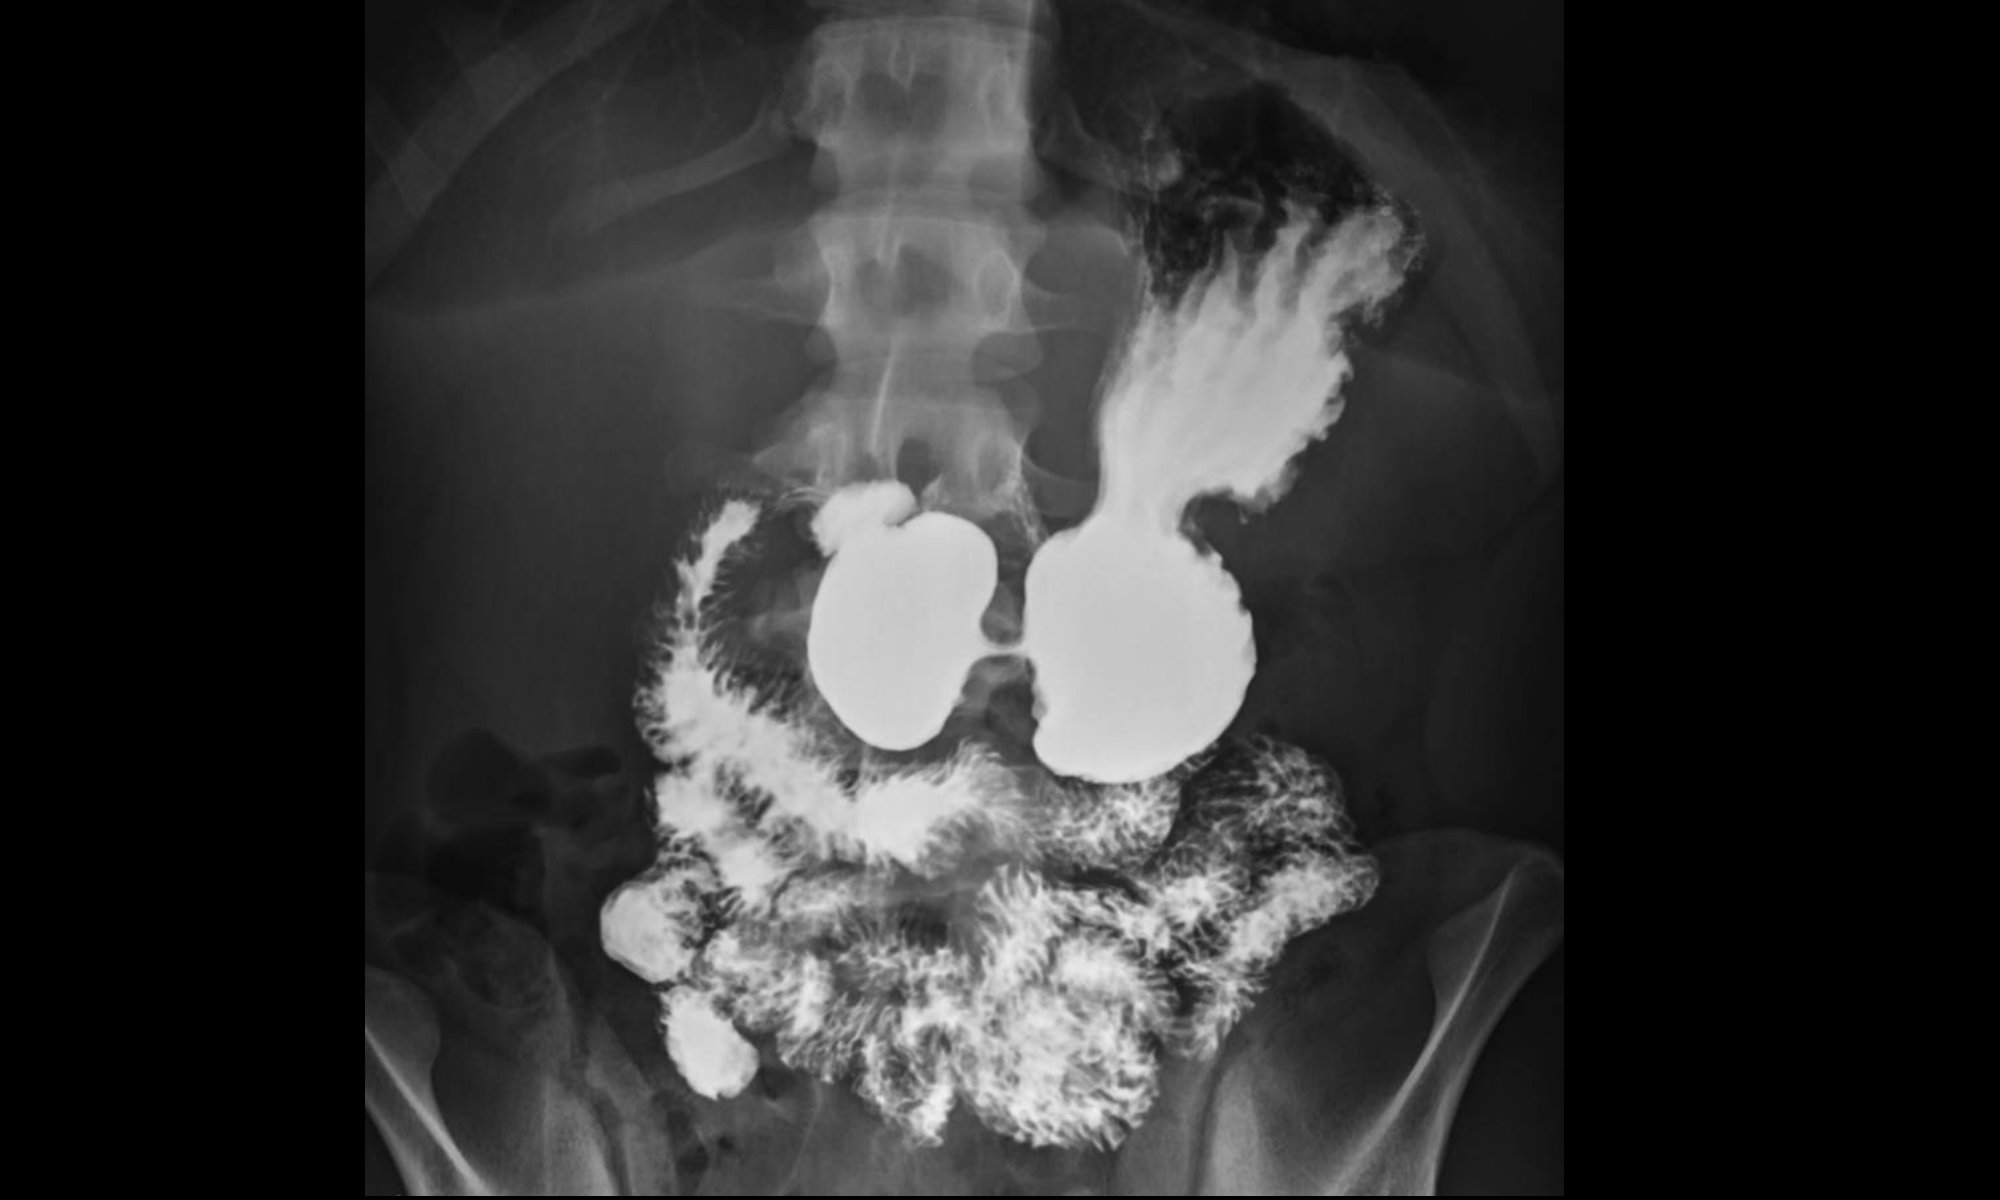

Transit oesophagien et gestro-duodénal (TOGD)

Cet examen permet de visualiser la progression d’un produit opaque au niveau de l’œsophage, de l’estomac et du duodénum et d’étudier les parois digestives.

Lors de l’examen, le manipulateur vous demandera d’ingérer le produit opaque à des moments précis. Il est important d’écouter les consignes du manipulateur afin d’obtenir un examen de bonne qualité.